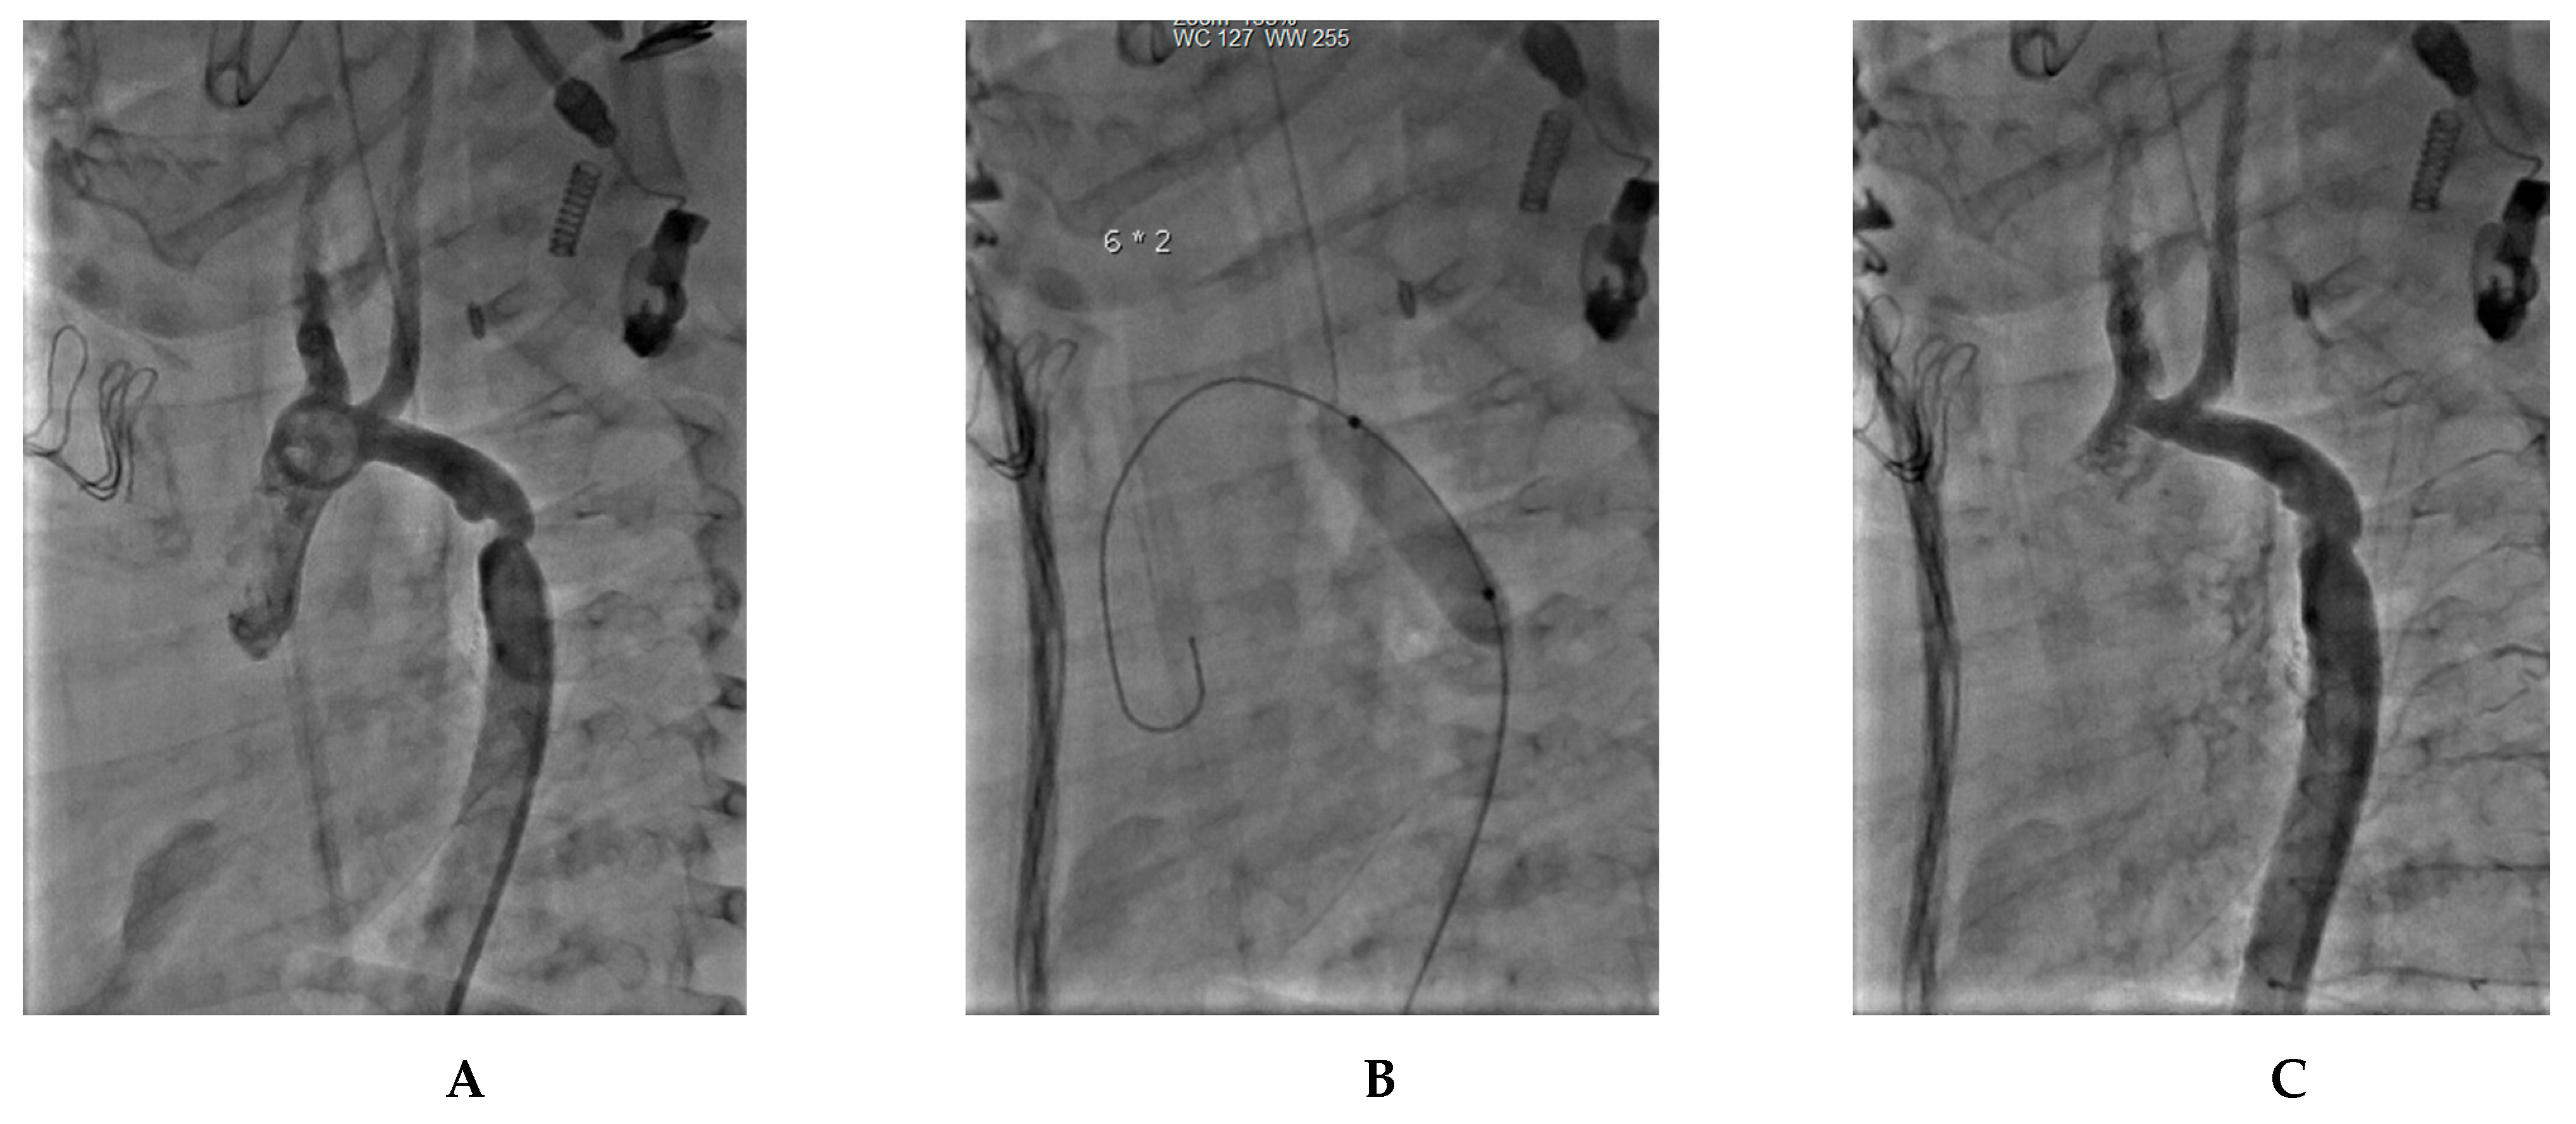

7. Our Experience-Case Series